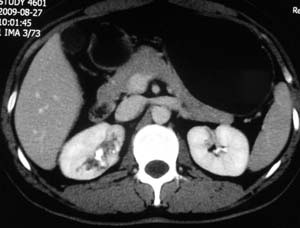

以下是引用子期在2010-3-19 20:47:00的发言:[br]血管畸形的ct增强应该有明显强化,本例并不相符合。本例双肾局部的略低密度影,累及肾盂,局部皮质明显变薄、内陷,增强扫描有轻度的强化,应考虑为炎性病变,患者为年轻男性,累及双肾的感染以结核较常见,可以没有明显的临床症状,尿中有时候也并不能查出什么;肾脓肿常有明显感染中毒症状,本例不符,另外一般的肾盂肾炎或肾小球肾炎通过小便就可确诊,其它还不能排除的是黄色肉芽肿性肾盂肾炎,然而单凭ct一般也很难鉴别。